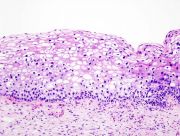

| 2021年7月26日 (一) 18:21 | Cervical intraepithelial neoplasia (2) koilocytosis.jpg (文件) |  |

85 KB | 77921020 | Uploaded with SimpleBatchUpload | 1 |